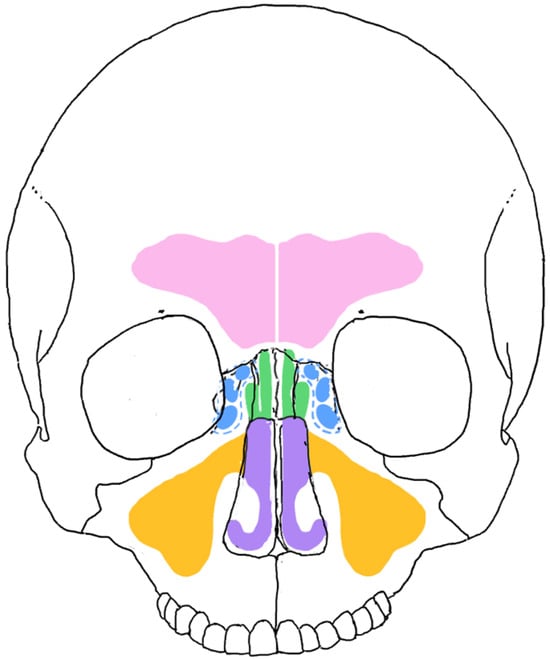

These sinuses play several important roles in the human body, encompassing both physiological and mechanical functions. They help to lighten the skull’s weight and enhance voice resonance. Additionally, they provide a cushioning effect against maxillofacial trauma, absorbing shock to protect the facial structures. Sinuses also humidify and warm the air we breathe and contribute to immunological functions [10,11,12] (Figure 1).

Figure 1. Location and general morphology of the frontal (pink), sphenoidal (green), ethmoidal (blue) and maxillary (orange), and the nasal cavity (purple).